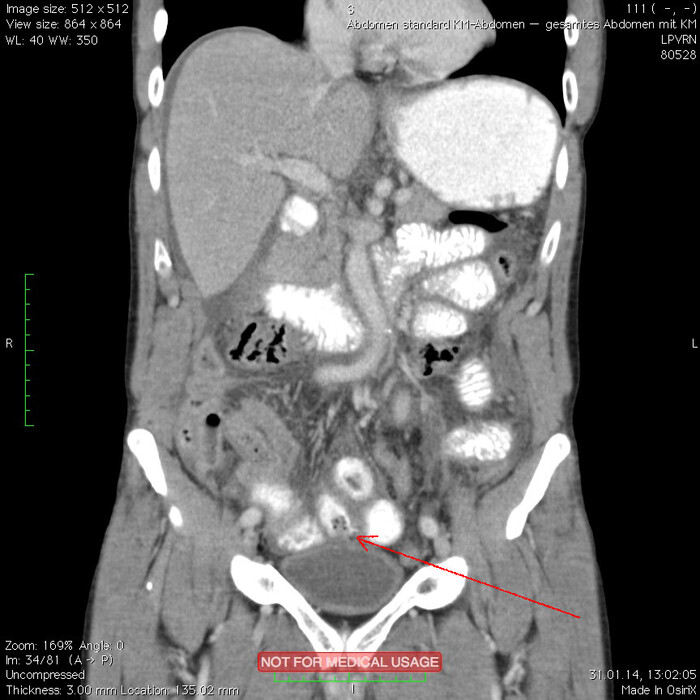

Мужчина, 32 года. Во время игры в футбол получил удар в низ живота, игру продолжил. Впоследствии боли в животе усиливались, стали нестерпимыми, ухудшилось общее самочувствие. На следующий день после игры пошёл сдаваться в больницу. Хирурги клинически описывают разлитой перитонит (воспаление брюшины) и отсылают пациента к нам на КТ, которое мы провели с внутривенной дачей контраста + заставили контраст ещё выпить (специальный раствор для перорального применения).

Так как клиника у нас острого живота после тупой травмы, учитывая что боли во всём животе и признаков большой кровопотери нет, то первое, что ищем - это свободный газ в брюшной полости, и находим его! (для этого лучше всего подходит т.н. лёгочное окно, как представлено ниже, или можно искать в костном окне - это спец.настройки яркости и контраста для просмотра разных структур тела - лёгкие, мозг, мягкие ткани, кости):

Отмечаем про себя, что в верхних квадрантах свободного газа не так уж и много. При перфорации желудка газа намного больше. Также выясняем, что газ есть также и в нижних квадрантах:

Ещё бросается в глаза массивный выпот (стрелки) во всех этажах, а также утолщение брюшины на всём протяжении, что указывает на диффузный (разлитой) перитонит. Тут, кстати, уже мягкотканное окно:

Итак, имеет место быть свободный газ в брюшной полости + свободная жидкость + перитонит. Определённо перфорация! Осталось найти источник. Желудок не подходит по механизму, а точнее по локализации травмы. Мочевой пузырь - в нём нет воздуха. Остаётся методом исключения только кишечник. Толстый или тонкий? Явно не верхние отделы толстого кишечника (ободочная кишка в области печеночного и селезеночного углов, а также поперечная исключаются - было бы больше воздуха). Сигма и нисходящая тоже заполнены стулом и воздухом. Получается, что тонкий кишечник всему виной.

Верхние (проксимальные) отделы точно не причём. Жидкость (звёздочки) больше в малом тазу, тут же и воздух. Для сравнения верхний этаж:

Hижний этаж:

И тут СТОП! А это чтo такое???

Кишке это точно не принадлежит, как ни крути. Это вышедший за пределы кишки контраст, который пациент выпил!

Осталось только место выхода найти:

Итого: перфорация тощей кишки в дистальных отделах, разлитой перитонит.

Был успешно прооперирован, место перфорации ушито, выписан.